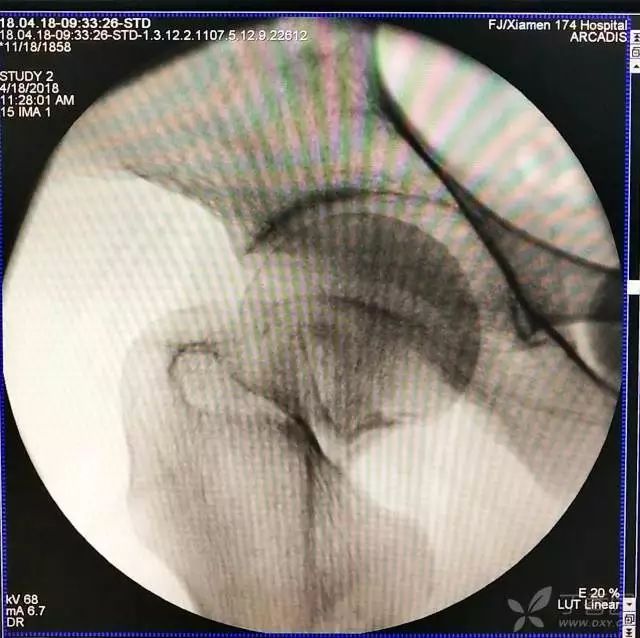

1. 对于难复性股骨颈骨折,术前应做好切开复位的准备,该患者复位三次都不太满意。

2. 倒数第二次的复位仍是欠缺一点

3. 再努力一把就基本成了

4. 先体外放置一枚导针导引进针方向

5. 打入第一枚倒品字下方导针,跟体外导针基本重叠